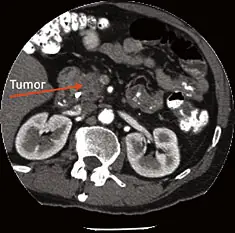

TOMOGRAFÍA COMPUTARIZADA Y TOMOGRAFÍA COMPUTARIZADA ESPIRAL O HELICOIDAL (CT SCAN, POR SUS SIGLAS EN INGLÉS)

Con el paciente recostado sobre una mesa, el escáner de tomografía computarizada en forma de anillo gira alrededor del cuerpo y toma imágenes radiográficas transversales de “rebanadas” del cuerpo. Luego, una computadora recopila las imágenes en series de detalladas láminas transversales del interior del cuerpo. Una reconstrucción tridimensional de estas imágenes también puede proporcionar información adicional.

A diferencia de una imagen de radiografía, que muestra sólo huesos, las imágenes de tomografía computarizada tienen la capacidad de mostrar tejido blando, vasos sanguíneos y huesos. Cuando se usa la tomografía computarizada con una sustancia como medio de contraste por vía intravenosa u oral, ésta puede mostrar la presencia de pequeños tumores pancreáticos y si el cáncer se ha diseminado.

Muchas máquinas de tomografía computarizada son ahora escáneres de tomografía computarizada helicoidal. En una tomografía computarizada helicoidal, el haz de rayos x permanece continuamente encendido y gira alrededor del paciente en un patrón espiral mientras el paciente está recostado en una mesa que se mueve lentamente. La tomografía computarizada helicoidal es más eficaz y produce imágenes tridimensionales que son más detalladas que las imágenes de tomografía computarizada convencionales.

Una tomografía computarizada es uno de los procedimientos de imágenes más comunes que se realiza cuando se sospecha que una persona tiene cáncer de páncreas. Las imágenes a menudo se usan para determinar si el tumor se puede extirpar quirúrgicamente o no. Un pequeño porcentaje de pacientes son alérgicos al medio de contraste, en cuyo caso se debe usar otro examen de imagen alternativo.

Debido a que la tomografía computarizada usa rayos x, a los pacientes y médicos les preocupa la exposición repetida a la radiación cuando ésta se usa para detección y vigilancia.

Donde se encuentre disponible, la tomografía espiral computarizada se prefiere a la tomografía convencional para la detección y estadificación del cáncer de páncreas. La tomografía espiral computarizada es útil para la estadificación debido a que proporciona más detalles anatómicos que pueden mostrar si el tumor se diseminó a los vasos sanguíneos cercanos.